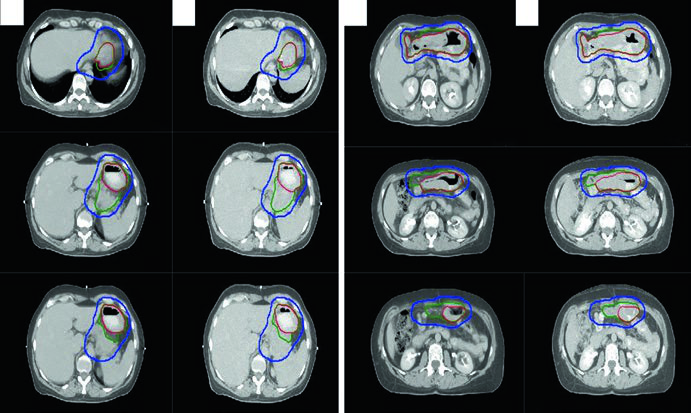

LH Avançado com Doença Bulky

Uma mulher de 31 anos com LH esclerose nodular estádio IIB bulky envolvendo linfonodos cervicais, supraclaviculares, mediastinais e hilares bilaterais recebeu 2 ciclos de ABVD (resposta completa no PET interim, Deauville 2), seguidos de 4 ciclos de AVD (Bleomicina descontinuada por toxicidade pulmonar). A RT consolidativa foi indicada pela doença bulky inicial.

O ITV final foi obtido por 4D-CT na simulação, contabilizando variações anatômicas respiratórias. A prescrição foi feita ao ITV mais a margem de PTV institucional. Esse caso demonstra como a ISRT adapta-se à anatomia pós-quimioterapia: o CTV respeita a extensão craniocaudal do GTV pré-quimio enquanto limita a exposição radial das estruturas normais adjacentes.